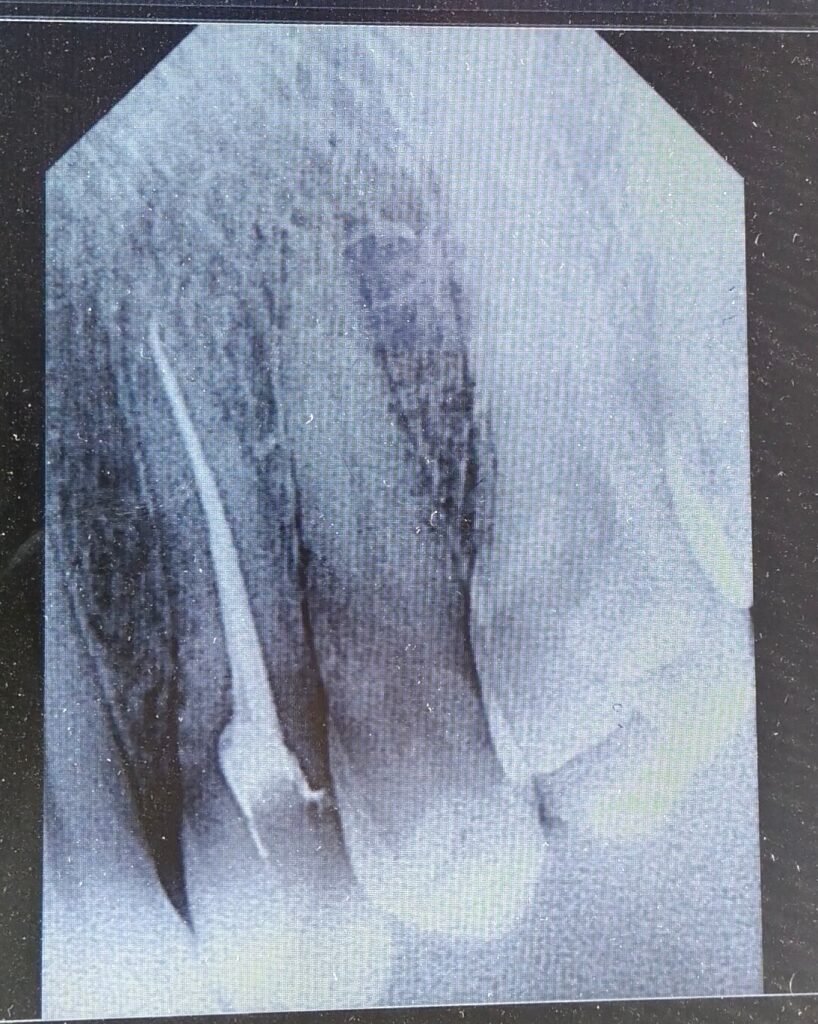

Utilizing rotary endodontics, we performed the RCT on Rahim’s upper right first premolar, known for often having two canals. In Rahim’s case, we confirmed the presence of two canals—the buccal canal measuring 21mm and the palatal canal measuring 22mm. Despite the complexity, the advanced techniques ensured precise treatment and Rahim’s comfort.

It’s crucial to note that the success of Root canal treatment depends significantly on proper technique. Using an X-ray and sensor from Eighteeth for working length confirmation of root canals, we ensured a precise understanding of the working length. In many failed RCT cases, under-obturation is observed, highlighting the importance of thoroughly cleaning the canal to the apex and then well-obturating it for a successful outcome.